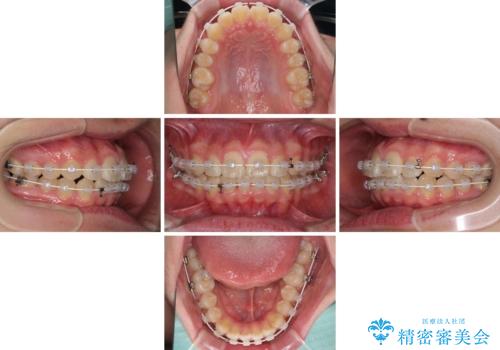

- 矯正装置

- 審美装置

- 上下前歯のデコボコを改善したいとのことで来院された患者様です。

自己管理を減らしたいとのことで、ワイヤー装置による矯正治療を行うこととしました。

中学生と言うこともあり、1年強の短期間で終了しました。

歯磨きがしっかりとできないと虫歯になるリスクがありましたが、治療期間中は清潔な状態を保っていただけました。